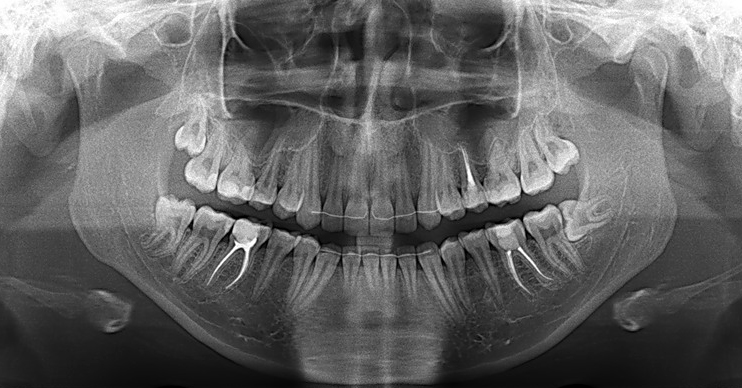

Фотографии ортопантомограмм и работ Родена